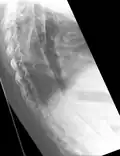

Fracture of the T5 and C7 vertebra due to trauma in a person with ankylosing spondylitis as seen on a CT scan

Prognosis is related to disease severity.[11] AS can range from mild to progressively debilitating and from medically controlled to refractory. Some cases may have times of active inflammation followed by times of remission resulting in minimal disability while others never have times of remission and have acute inflammation and pain, leading to significant disability.[11] As the disease progresses, it can cause the vertebrae and the lumbosacral joint to ossify, resulting in the fusion of the spine.[44] This places the spine in a vulnerable state because it becomes one bone, which causes it to lose its range of motion as well as putting it at risk for spinal fractures. This not only limits mobility but reduces the affected person's quality of life. Complete fusion of the spine can lead to a reduced range of motion and increased pain, as well as total joint destruction which could necessitate a joint replacement.[45]

Osteoporosis is common in ankylosing spondylitis, both from chronic systemic inflammation and decreased mobility resulting from AS. Over a long-term period, osteopenia or osteoporosis of the AP spine may occur, causing eventual compression fractures and a back "hump".[46] Hyperkyphosis from ankylosing spondylitis can also lead to impairment in mobility and balance, as well as impaired peripheral vision, which increases the risk of falls which can cause fracture of already-fragile vertebrae.[46] Typical signs of progressed AS are the visible formation of syndesmophytes on X-rays and abnormal bone outgrowths similar to osteophytes affecting the spine. In compression fractures of the vertebrae, paresthesia is a complication due to the inflammation of the tissue surrounding nerves.